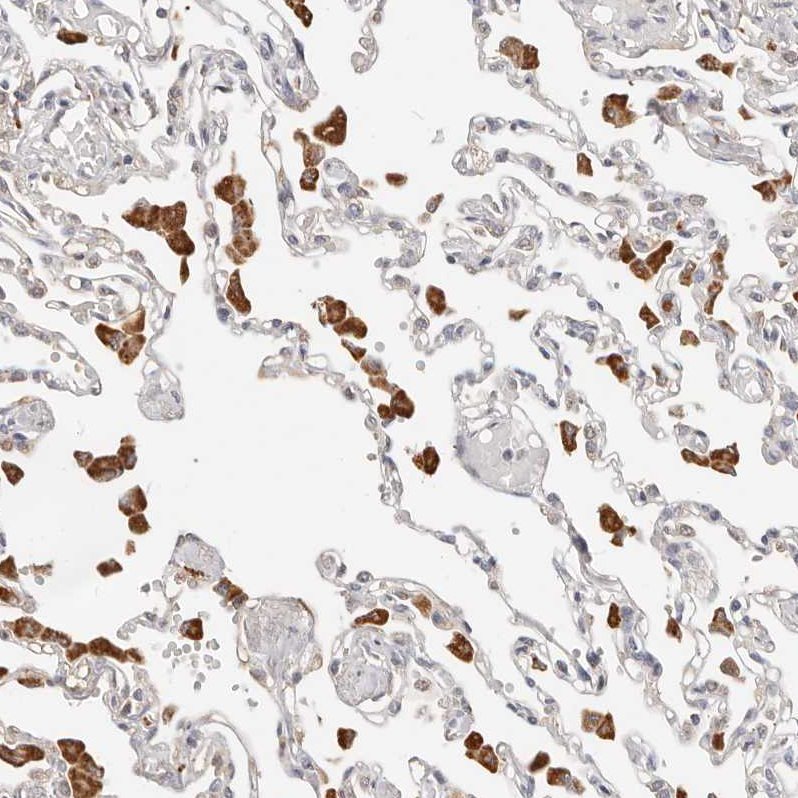

Immunohistochemical staining of human testis shows strong nuclear positivity in cells in seminiferous ducts.